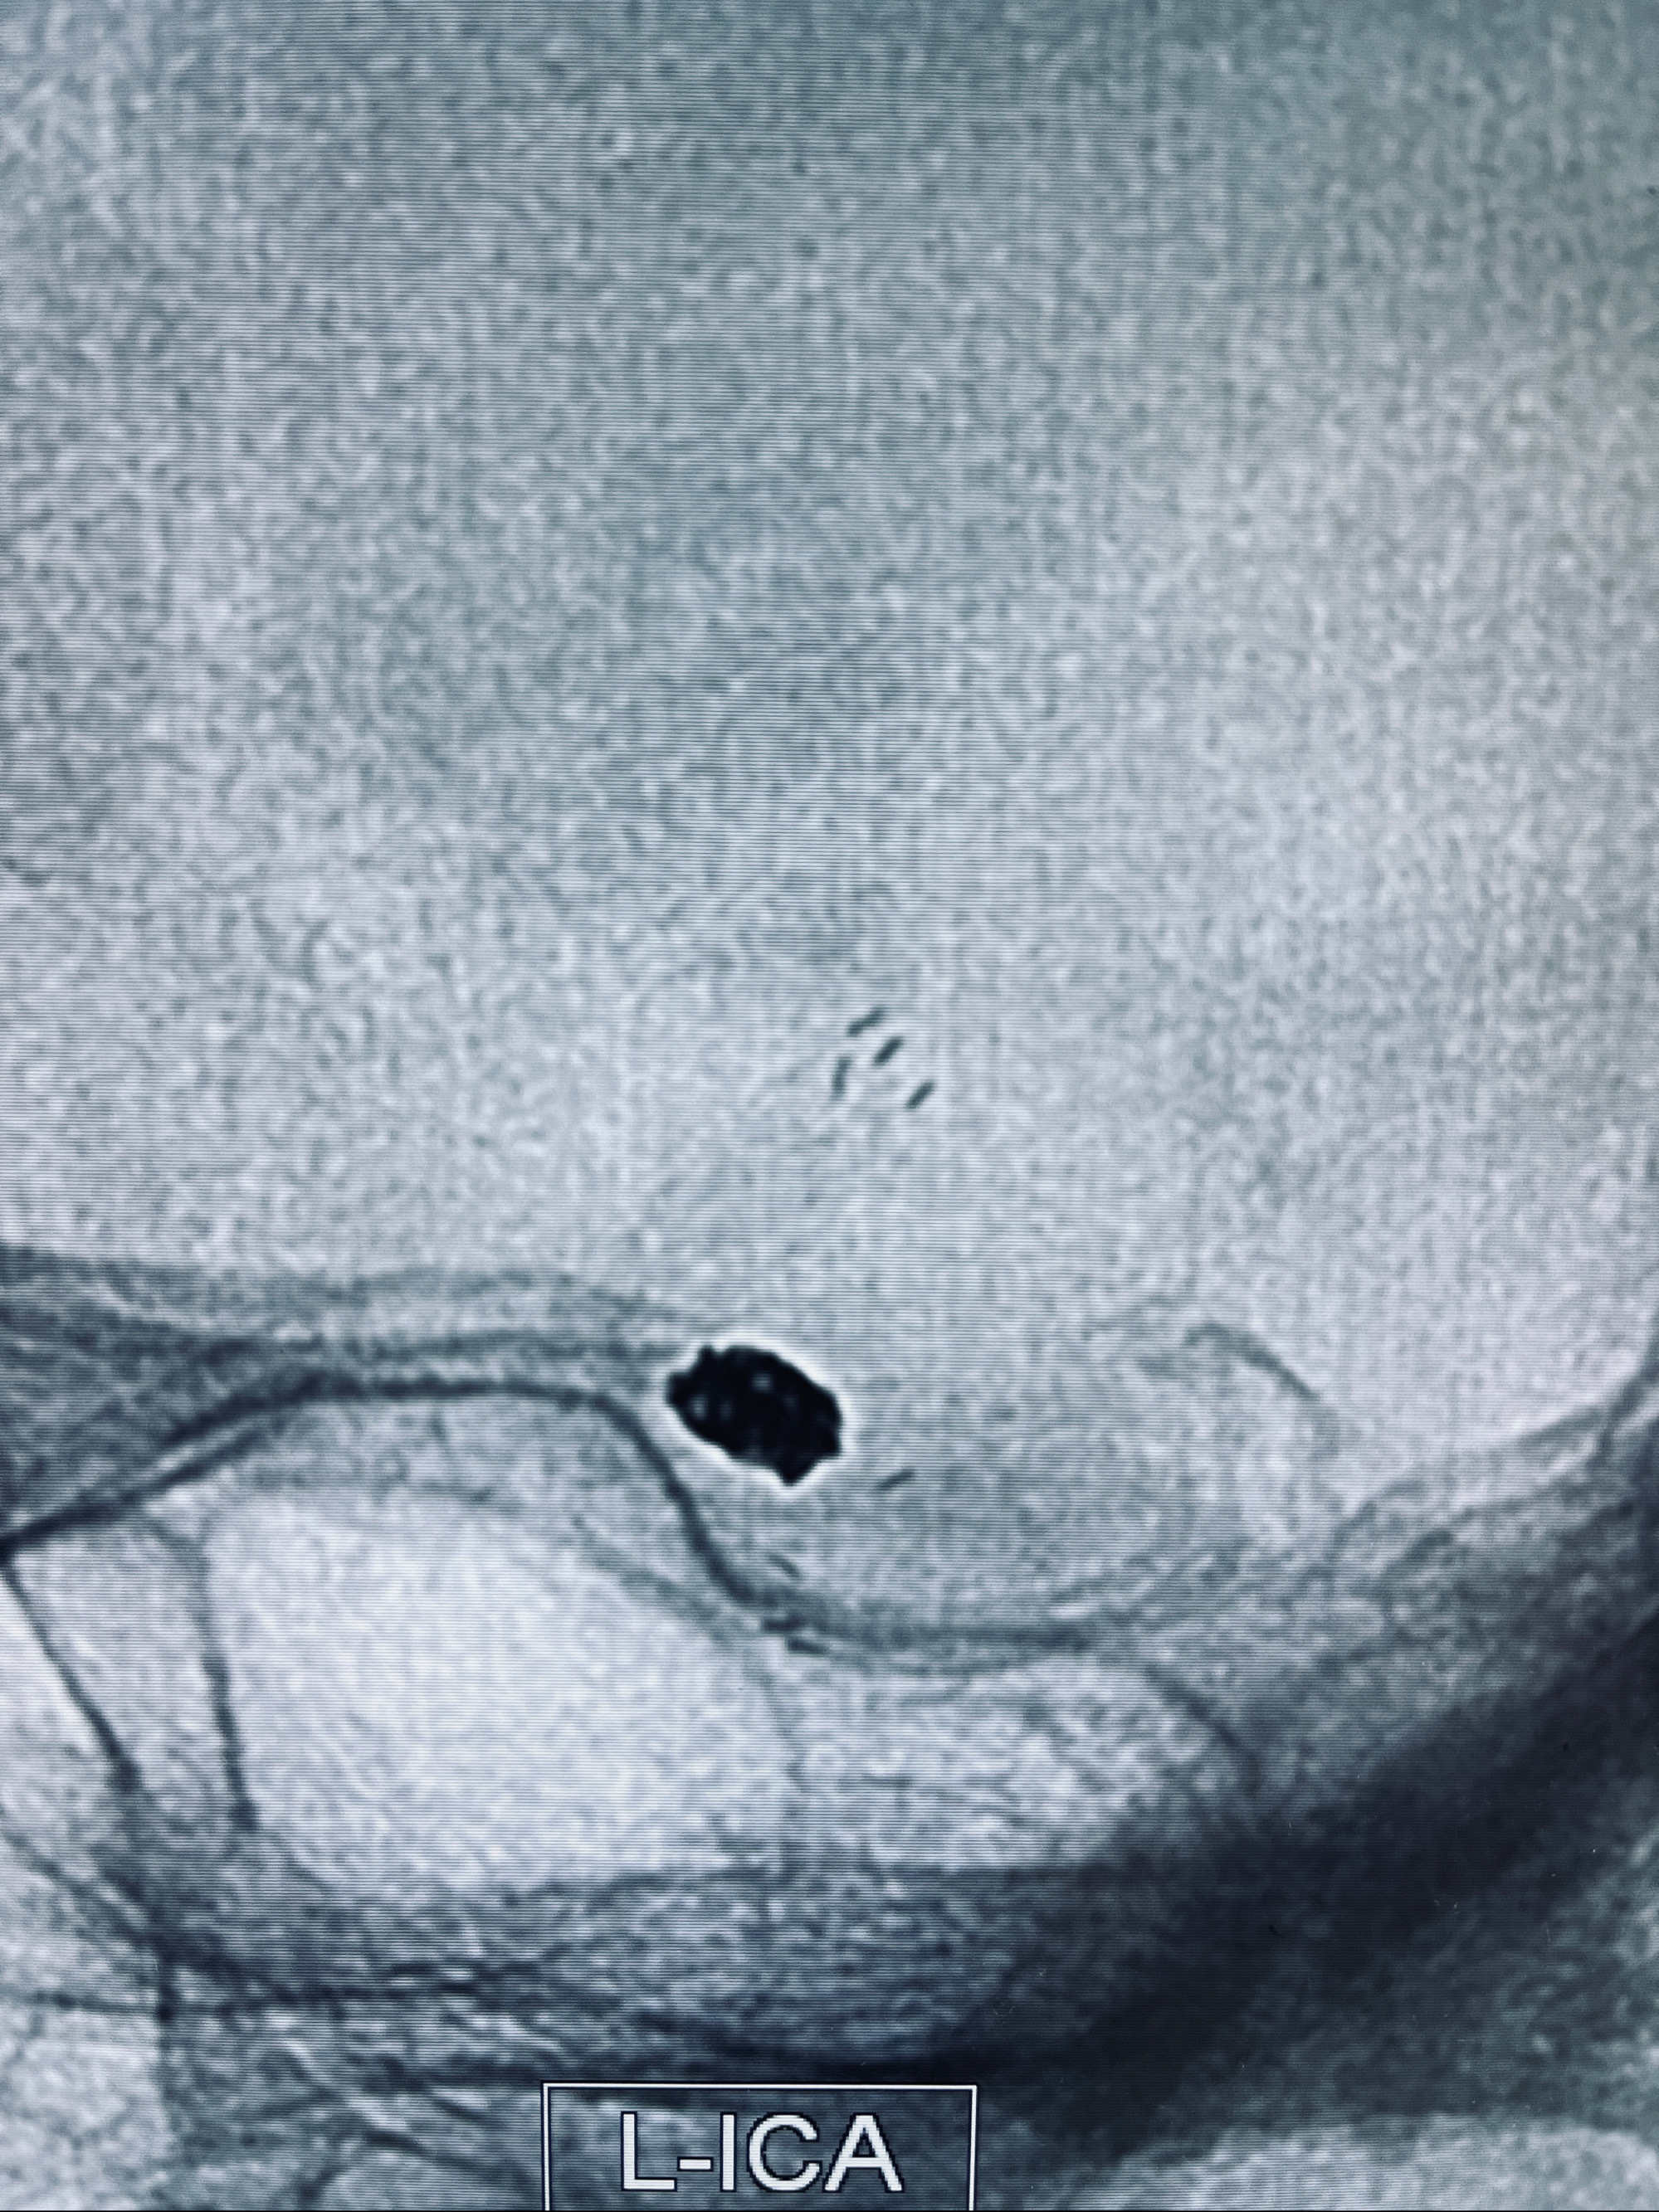

现病史:患者,女,因“左侧颈眼动脉瘤支架辅助栓塞术后1年余”入院。患者2021-5-24因“头晕”就诊于华山医院查头颅CTA、DSA诊断左侧颈眼动脉瘤,随后在全麻下行“左侧颈眼动脉瘤支架辅助栓塞术”,术顺,术后恢复可,予以阿司匹林、氯吡格雷抗血小板,阿托伐他汀钙片降脂稳定斑块。3月后华山医院复查脑血管造影动脉瘤未见明显复发或残留,停用降脂药物。目前患者无明显不适主诉,口服阿司匹林抗血小板治疗,为行脑血管造影收入我科。

1.左侧颈内动脉眼动脉段动脉瘤(支架辅助栓塞术后)

2022-09-29复查DSA